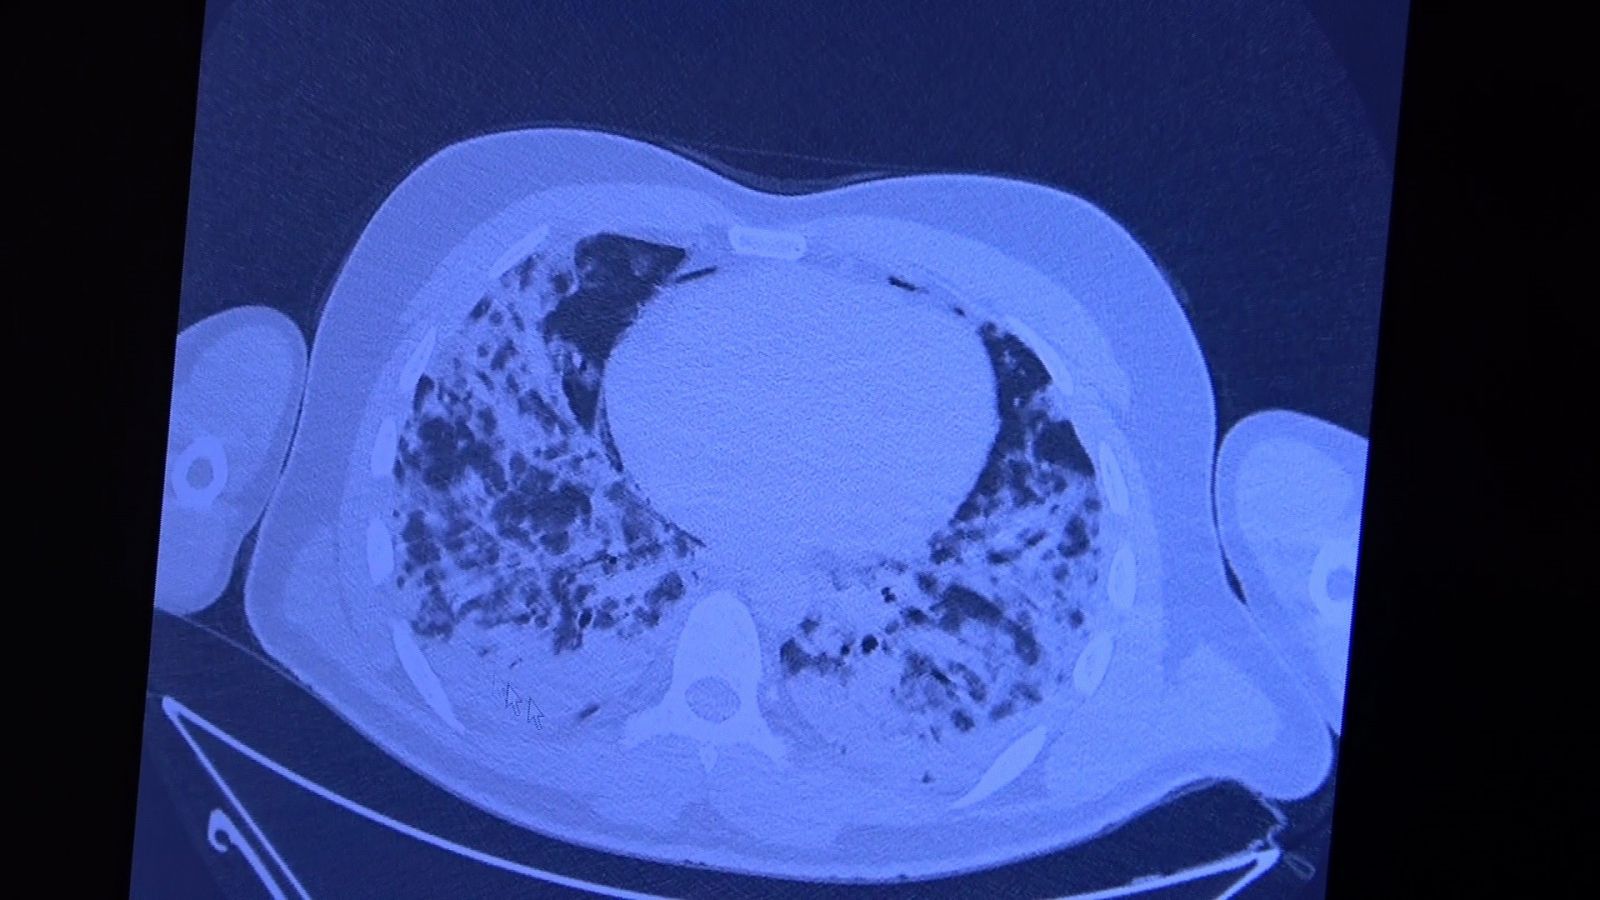

Aşı olmamış ve akciğer tutulumu yaşamış 30'lu yaşlardaki hastaların durumlarını aktaran Özkaya, "Şu an şunu söyleyebilirim ki eğer Covid'e yakalanırsanız hayatta kalıp kalmayacağınızın tek göstergesi aşı olup olmadığınızdır. Polikliniğe pozitif bir hasta geldiğinde aşı olmamışsa biz korkuyoruz çünkü hastayı kaybetme riski var. Bu korkuyu siz yaşamayın ve sevdiklerinize de yaşatmayın. Sizlere aşı olmamış 30'lu yaşlarda 2 tane hasta göstereceğim. Çeşitli mazeretlerle aşısını geçiştirmiş ve Covid'e yakalanmış. 30'lu yaşlarda akciğer tutulumu ile gelen genç bir hasta var. 10 gün içinde ciddi akciğer tutulumu oldu. Solunum yetmezliği gelişti ve yoğun bakımda yatırmak zorunda kaldık. Ciddi akciğer parçalanması yaşadık. Şu ana bu hasta hayatta ve kurtuldu. Bu hastanın hayatta kalması şanstı. Çok pişman oldu. 'Keşke aşımı olsaydım' dedi. Aşısı yaparak taburcu ettik" şeklinde konuştu.